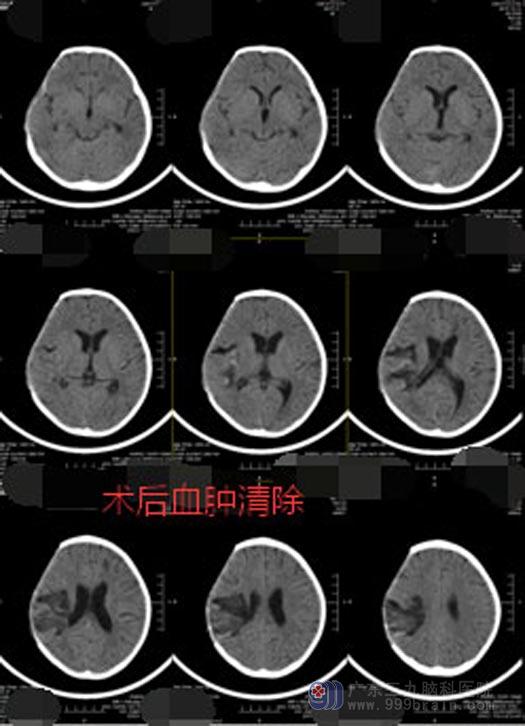

家人当机立断,连夜将珊珊送到了广东三九脑科医院神经外五科。入院时,她的双侧瞳孔已散大,不能发声、不能睁眼,刺痛肢屈。珊珊已经出现了脑疝,随时可能呼吸心跳骤停。当天值班的李医生立即向鲁明主任汇报患者病情并开通了绿色通道,在短短的半小时内就将珊珊送入了手术室,在全麻下行“血肿清除术+去骨瓣减压+气管切开术”,手术持续近6个小时。手术后,珊珊的瞳孔对光反射灵敏,“暂时算是把命保住了”。